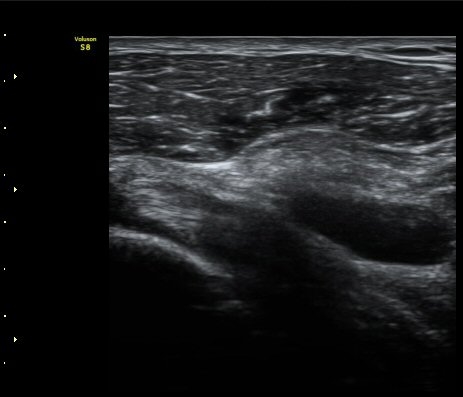

±Ø»ó°Ç Á¾´Ü¸é°Ë»ç»ó ±Ø»ó°Ç ³»Ãø ºÎÂøºÎ¿¡¼­ °Ç¿¬°á¼º ¼Ò½ÇÀÌ °üÂûµÈ´Ù(±×¸² 7, 8).

±Ø»ó°Ç Á¾´Ü¸é°Ë»ç»ó ±Ø»ó°Ç ¼Ò½Ç¿¡ ÀÇÇÑ È¸Àü±Ù°³ °á¼ÕÀÌ °üÂûµÈ´Ù(±×¸² 9, 10).